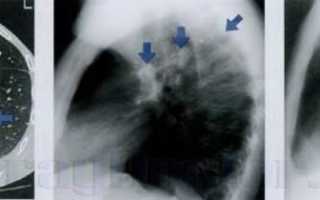

Рентгенография: Туберкулез легких

Туберкулез

Туберкулез — инфекционное заболевание, вызываемое микобактериями туберкулеза, преимущественно Mycobacterium bovis и Mycobacterium tuberculosis. Заболевание проявляется образованием специфических гранулем в различных тканях и органах.

Рентгенологическая картина туберкулеза легких разнообразна и зависит от формы, стадии и периода болезни (первичный или вторичный), а также от наличия осложнений. У пациентов с иммунодефицитом, особенно при ВИЧ-инфекции, наблюдается нетипичная рентгенологическая картина.

В данной статье рассмотрим некоторые аспекты рентгенологической диагностики вторичного туберкулеза легких у взрослых.

Вторичный туберкулез имеет несколько характерных особенностей:

• Локализация в верхне-задних сегментах легких (S 1, 2, 6).

• Образование полостей распада в инфильтратах.

• Формирование каверн.

• Наличие очаговых изменений.

• Образование очагов отсева в пораженных и противоположных легких.

Рисунок 1. Локализация изменений на рентгенограмме, характерная для вторичного туберкулеза легких (в прямой и боковой проекциях): S 1, S 2 верхней доли и S 6 нижней доли.

Рисунок 2. Туберкулезный процесс в легких (схематическое изображение): в верхних отделах правого легкого инфильтрация с полостями распада; на фоне инфильтрации отдельные очаги. Очаги отсева (очаговые тени) также могут определяться в отдаленных участках пораженного и противоположного легкого. Рентгенограмма соответствует инфильтративному туберкулезу правого легкого в фазе распада и обсеменения.